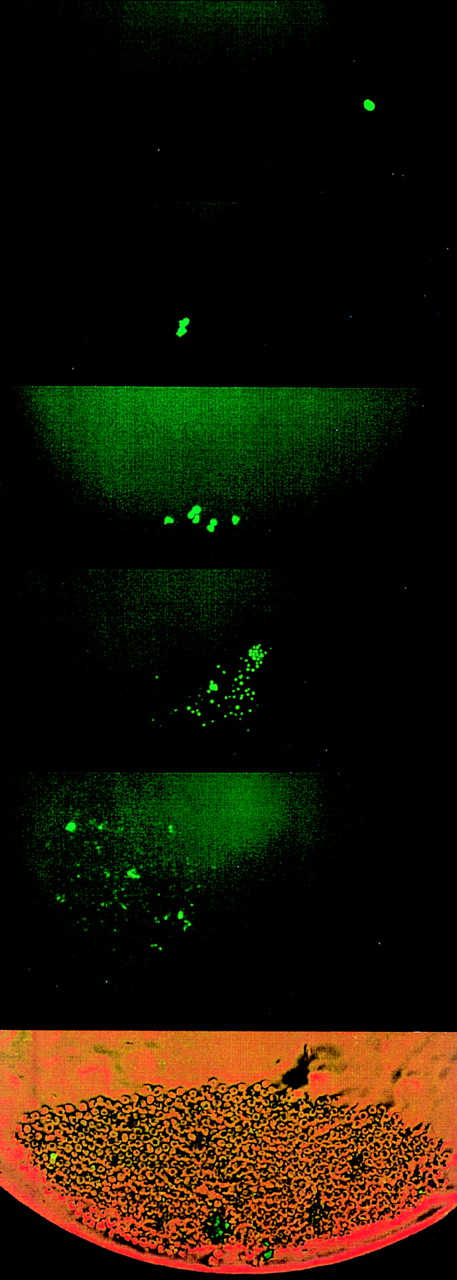

Divisional history of 1 single CD34+/CD38− cell stained with PKH26, derived from an FLV sample. At 0 hour, a cell showing bright fluorescence is depicted. At 38 hours, the cell has divided, yielding 2 daughter cells with bright PHK26 fluorescence. At 98 hours, 1 cell has maintained bright fluorescence among 32 cells with dim fluorescence. On day 8 (at 194 hours), 1 cell with bright fluorescence has remained among several hundreds of other cells. The upper 4 pictures were taken with fluorescence microscopy. The bottom picture shows the same cell culture on day 8 in both phase contrast and fluorescence microscopy.

Figure 2 demonstrates the divisional history of 1 single CD34+/CD38− cell that has divided asymmetrically, as monitored by time-lapse camera system over a period of 8 days. In the first 36 to 38 hours, the image confirmed that 1 single cell with very bright fluorescence was deposited in the well. After 36 to 38 hours, 2 cells with bright PKH26 fluorescence were observed. Seventy-two to 74 hours after culturing, 1 bright cell was observed among 8 other cells with dim fluorescence. Whereas the 1 PKH26 bright cell maintained its fluorescence intensity and remained quiescent, the other cells continued to divide symmetrically to give rise to 16, 32, 64 cells, etc, every 12 hours, such that on day 8, the same bright cell was observed among hundreds of fluorescence-negative cells, thus providing evidence that asymmetric divisions occurred among CD34+/CD38− cells derived from FLV. Other CD34+/CD38− cells initially gave rise to 2 daughter cells that appeared equivalent after the first mitosis, but then divided asymmetrically after the second division. Figure 3 shows a typical example, ie, 1 parental cell gave rise to 2 daughter cells, which in turn gave rise to 4 cells, with 1 of 4 cells then remaining quiescent, whereas the other 3 multiplied symmetrically, giving rise to altogether 7 (6 + 1) cells at 60 hours after culturing. We have analyzed the percentages of asymmetric divisions found after the first, second, third, and up to the fifth cell division. The results of 4 experiments are summarized in Fig 4. Forty-two percent and 25% of all the asymmetric divisions occurred during the first and second mitosis, respectively. Asymmetric divisions are rarely found in the third (13%), fourth (13%), and fifth (7%) waves of cellular divisions.